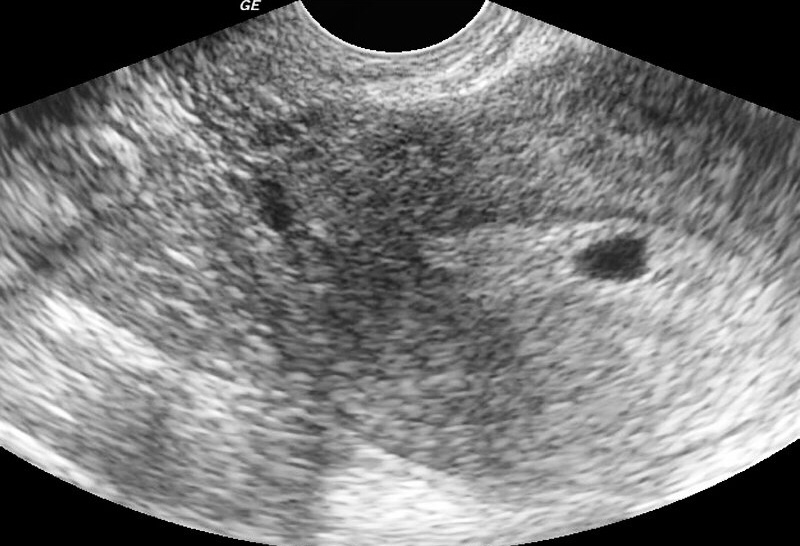

Двойня!!! 8 недель 😫

ВНЕМАТОЧНОЙ!!!